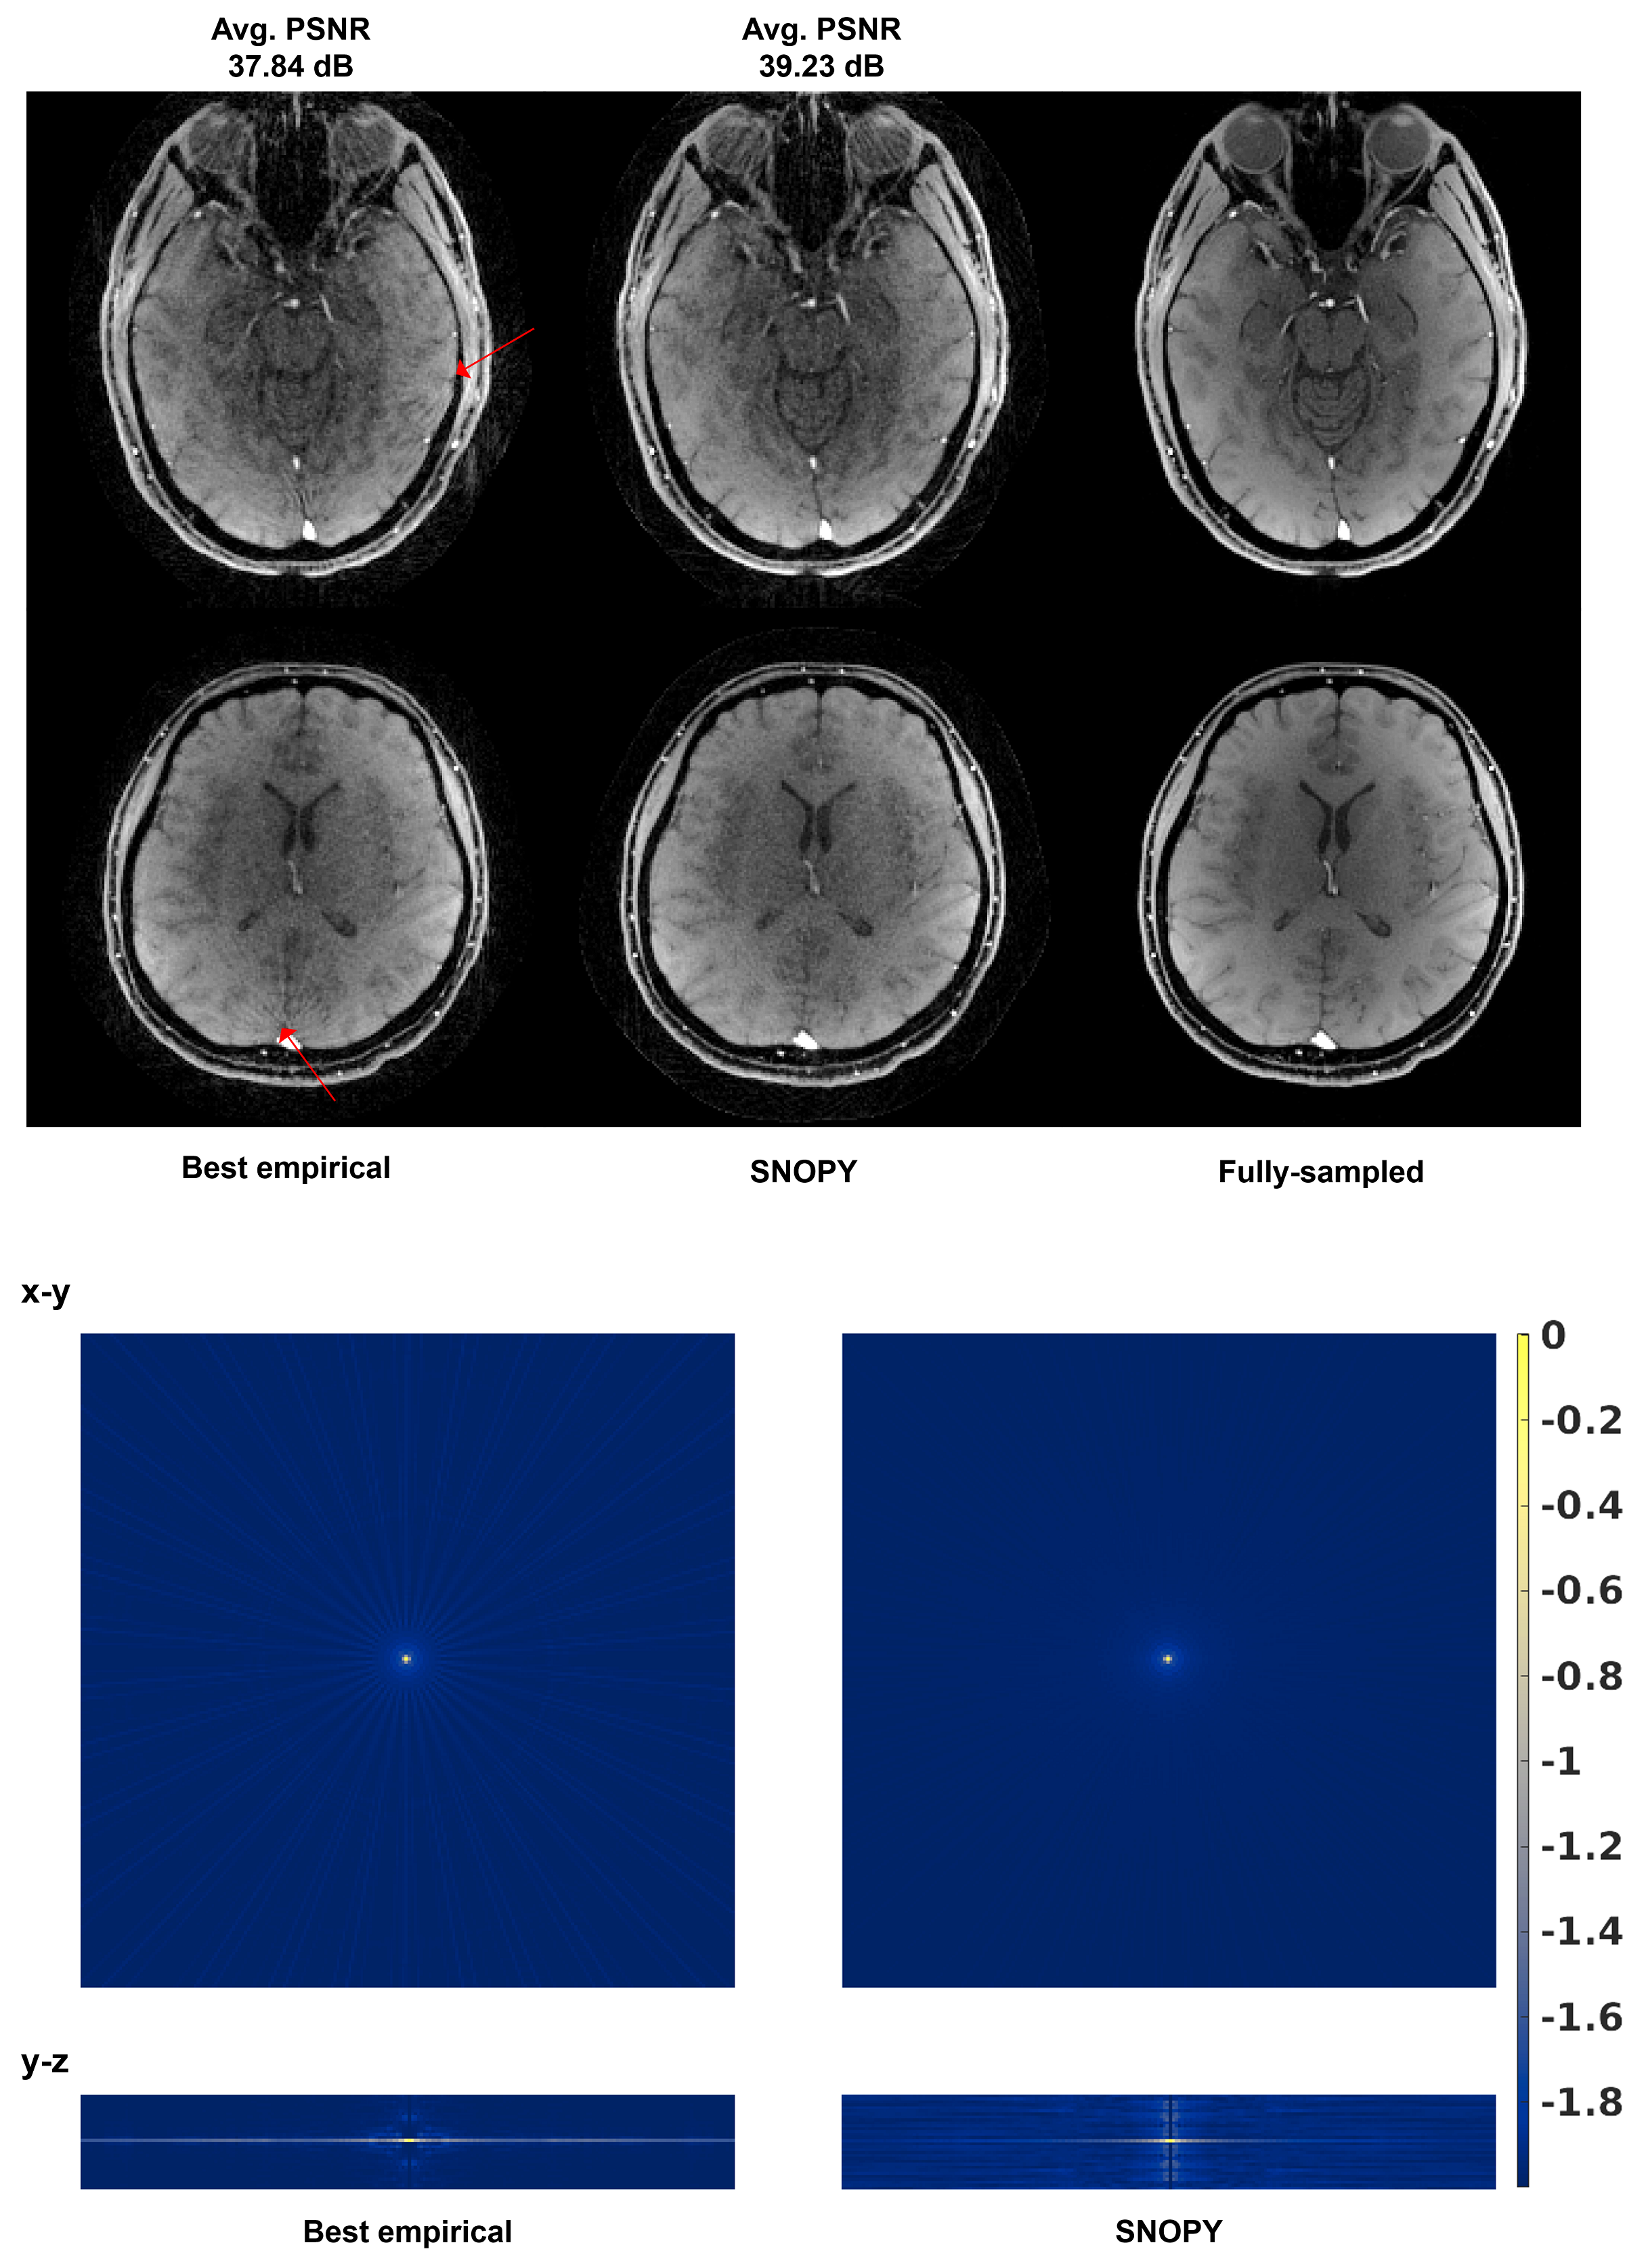

For the spline-based freeform optimization experiment, Table 1 (b) shows the quantitative image quality in the simulation experiment. Across reconstruction methods (CG-SENSE and model-based deep learning, MoDL [9]), SNOPY improved image quality (PSNR) by ~4dB. Fig. 2 shows example slices. Fig. 3 shows the prospective results of experiment 2, optimization of rotational angles of SOS. SNOPY effectively reduced streak artifacts. PSFs of different trajectories also support this finding. Fig 4 displays the PNS effect reduction brought by SNOPY both in simulation studies and patients’ ratings (exp. 3). SNOPY efficiently reduced the severe PNS effect of REPI.

Figure 4. Results of experiment 2, optimizing the rotation angles of the stack-of-stars (6× acceleration). ‘Best empirical’ uses the design from a previous study [4]. We also labeled the average PSNR of the 4 subjects compared to the fully sampled reference. The lower subfigure shows the log-scaled PSF (single-coil) of two trajectories.